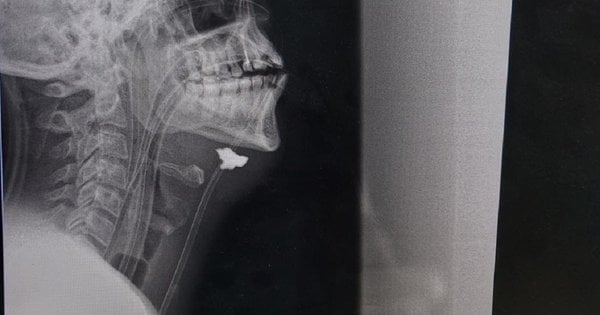

“Nakon pregleda, pacijentu je dijagnosticirana rana od metka i šrapnela. Fragment je pronađen u projekciji vaskularnog snopa, hematoma i znakova ozljede karotidne arterije s desne strane. Drugim riječima, fragment projektila pogodio je rame, prošao kroz cijeli vrat, puknuo karotidnu arteriju i zaustavio se ispod čeljusti”, rekao nam je Taras Kobza, vaskularni kirurg koji već duže vrijeme spašava vojnike na istoku zemlje.

Kako su objasnili vaskularni kirurzi u Lavovu, vrlo je teško spasiti pacijente s ozljedama karotidne arterije, mogu umrijeti doslovno za 5-10 minuta od trenutka ozljede zbog velikog gubitka krvi ili dobiti moždani udar. Kapetan je primljen u bolnicu nekoliko sati nakon što je ranjen. Prema kirurgu, spasila ga je činjenica da su se na mjestu rupture karotidne arterije stvorili krvni ugrušci (zaštitna reakcija tijela), što je zatvorilo lumen posude i donekle usporilo krvarenje. Ali izgubio je puno krvi.